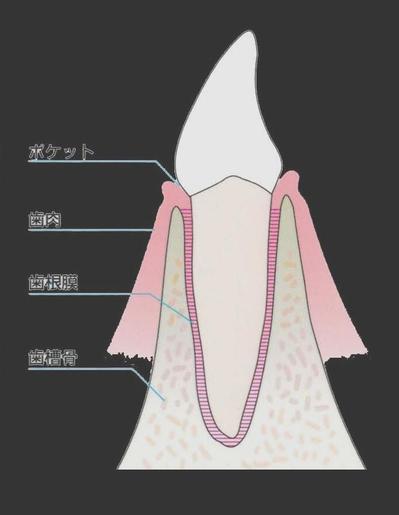

私はいつも患者さんに

「歯は大根が土に埋まっていると思って下さい」

とお伝えしています。

歯を支えているのは歯茎ではなく骨なんです。

この図でいえば

大根が歯、

黄土色部分が、骨です。

大根も顔の頭が見えているのは3分の1程度で

残りに3分の2は骨に埋まっています。

このようになっています。

これは歯がある方の場合です。

では、

歯を抜かないといけなくなり、

抜歯した場合にはどうなるでしょうか?

歯である大根部分が抜けた時の骨の状態です。

骨の上には歯茎があります。

白い部分が骨です。

骨の上に覆いかぶさっているピンク色の部分が歯茎です。

入れ歯はこの歯茎の上に

乗せているだけ、です。

場所によって、歯茎の厚みが違うのです。